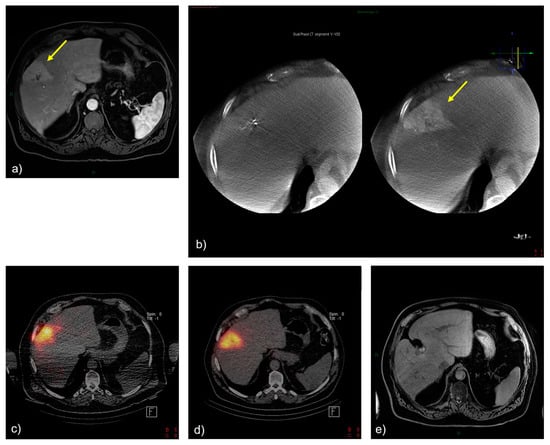

4. Discussion